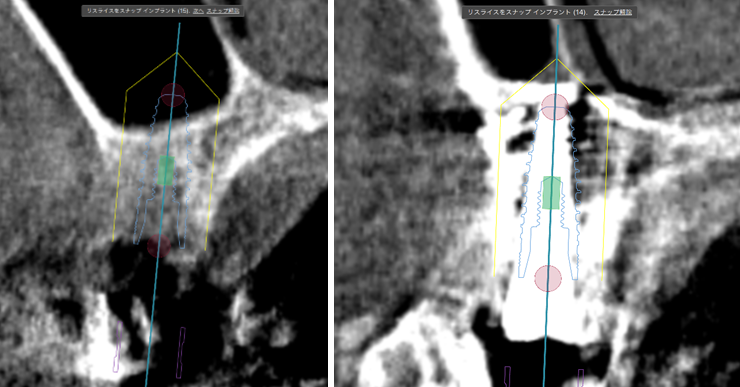

術前ではインプラントを埋入する骨組織はほとんど有りませんが、

術後完全に骨内に埋入出来ました。